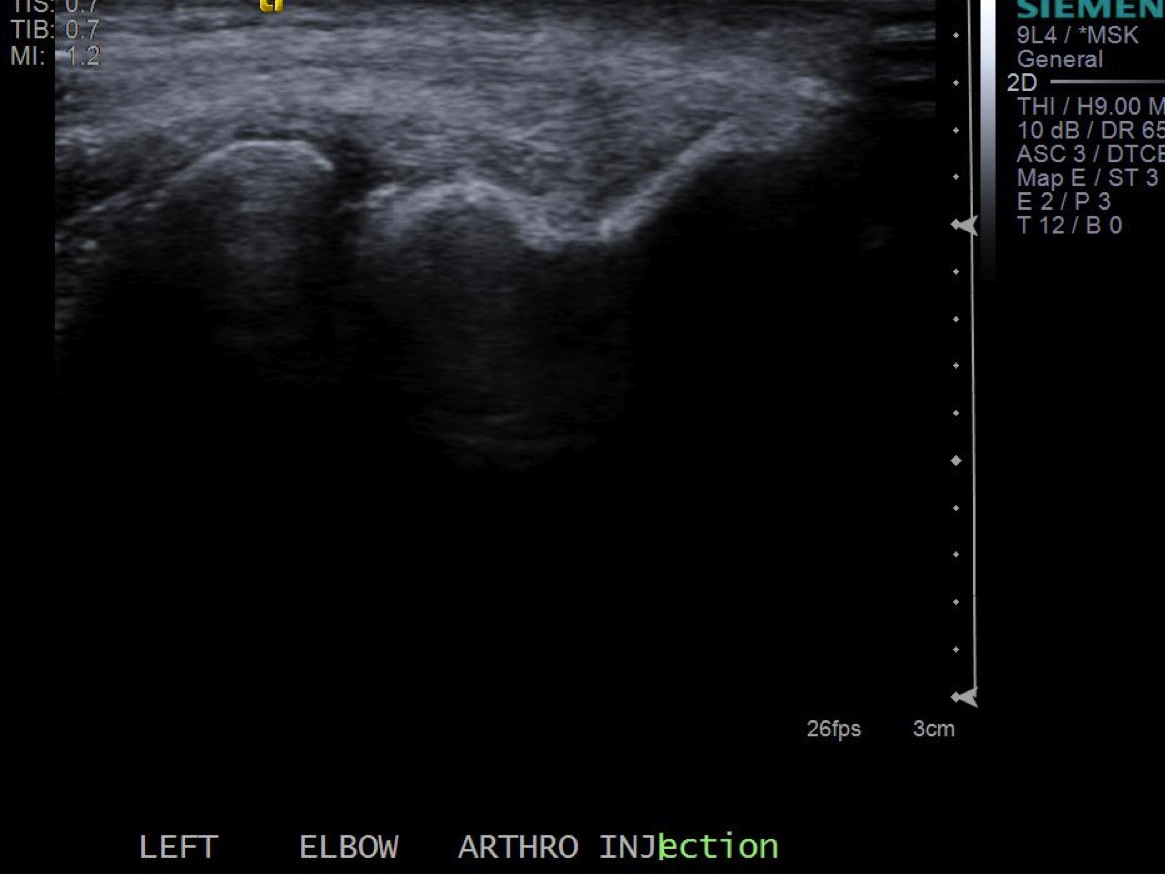

Picture of probe overlying the radiocapitellar joint. |

| 3. Place probe perpendicular to the joint and mark probe location and probable injection site |